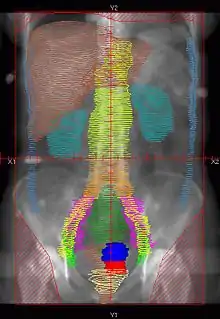

![]() |

Example of a AP whole abdomen/pelvis radiation therapy treatment field used at Tufts/Brown residency program. Actual patient contours should guide field design.

Example of a PA whole abdomen/pelvis radiation therapy treatment field used at Tufts/Brown residency program. Actual patient contours should guide field design.